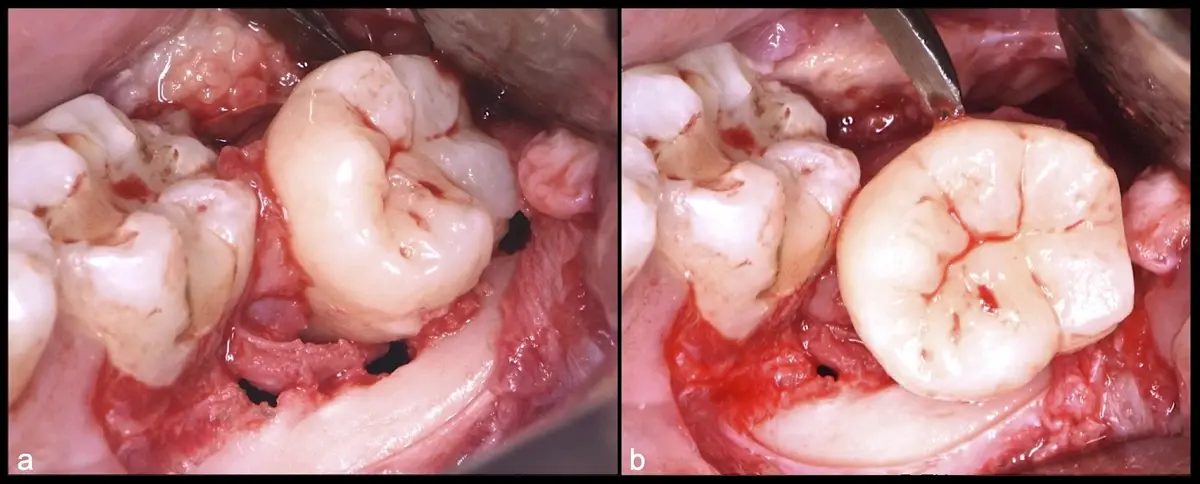

Para realizar la técnica de extracción de una tercera molar, una vez que se ha confirmado su diagnóstico, se debe considerar la posición del diente (vertical, mesioangular, distoangular, horizontal u otras), profundidad y grado de impacto, obstrucción a la erupción asociada a la segunda molar, morfología de la raíz (la curvatura de las raíces controla el camino de la exodoncia), relación con el canal del conducto dentario inferior, la patología asociada, la densidad ósea y la Integridad de la segunda molar.

El procedimiento se inicia colocando anestesia troncular para bloqueo del nervio dentario inferior y sus ramas. Luego, se establecerá el diseño de acceso según la disposición de la molar a extraer. Para fines didácticos, se explicará cómo se realizaría la extracción de la molar de la Figura 1: se realiza una incisión horizontal a nivel de la zona retromolar hasta llegar a distal de la segunda molar, continuándose con una incisión intrasurcular hasta mesial de la segunda molar, finalizando con una incisión vertical a espesor total hasta llegar a la línea mucogingival (Figura 2).